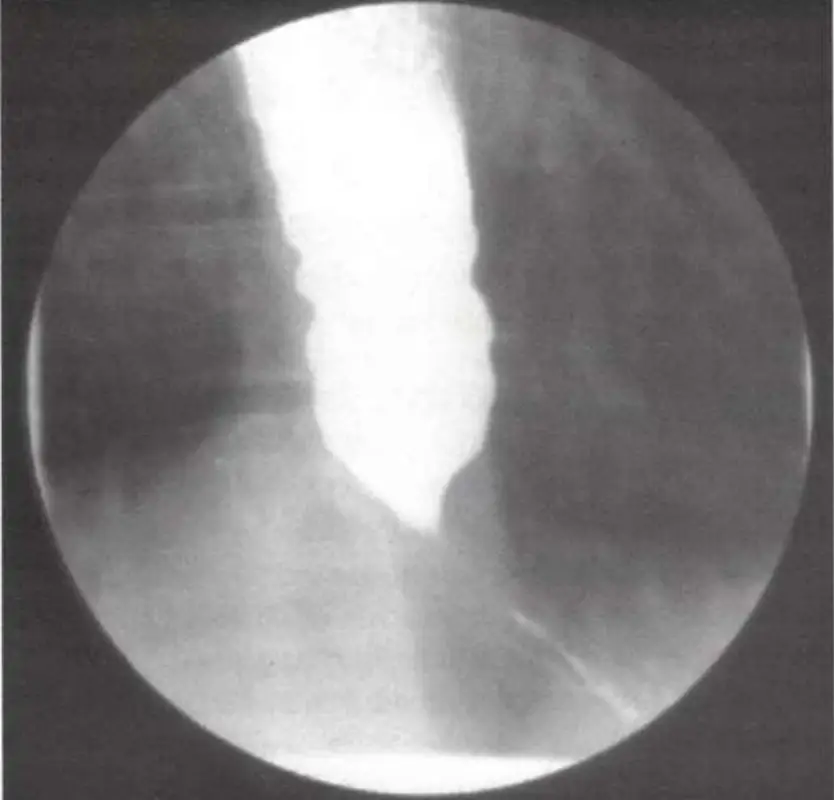

- 由放大影像可見:食管遠端呈現平滑、對稱的錐形狹窄,俗稱「bird’s-beak」或「rat-tail」徵象,下食道括約肌部位對比劑通過困難,上方對比劑柱狀積滯,並無典型 corkscrew(rosary-bead)結構、也未見食管出現多發性同步性痙攣的環狀收縮。

- 這種形態與「diffuse esophageal spasm」的 corkscrew 影像不同,符合「achalasia」典型早期表現,強調 LES 放鬆不足與食管體部失去有效蠕動。